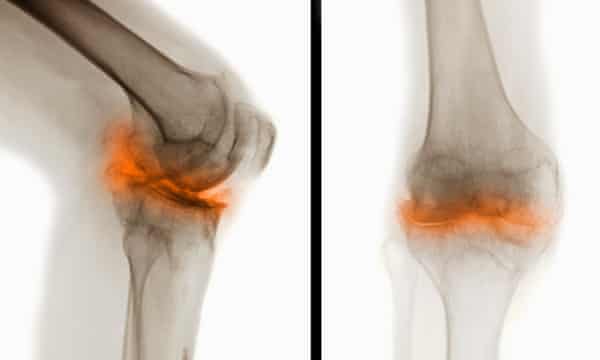

An important part of managing osteoarthritis knee pain is working with your doctor. It sounds contradictory but movement and exercise will ultimately free you from. Moderate knee arthritis can be treated aggressively with three to five injections of hyaluronic acid over three to five weeks time. In addition to treatments your doctor provides there are safe and effective ways you can treat knee arthritis at home. How do i get rid of arthritis in my knees Although there is no cure for knee arthritis there are treatments available to help you to keep moving. Home remedy to get rid of knee pain arthritis naturally is ready for use now. Examples of knee arthritis care at home include. To anyone with arthritis especially of the knee getting the right kinds of exercise daily is vital to your health. Rowe shows how to get rid of arthritic knee pain in 30 seconds or less AT HOME. Advil Aleve can help ease pain. Pain swelling stiffness and tenderness are the main symptoms. You may also use it at night after dinner before sleeping to get rid of knee pain and arthritis. Geier video I discuss surgical and non-surgical treatment options if you have no cartilage left in your knees.

Improving range of motion and strength in the knee are helpful but physical therapy for knee osteoarthritis has a large focus on strengthening the hips explains Dr. Applying heat or ice to the knee joint to reduce inflammation. Suffering From Arthritis In The Knee.